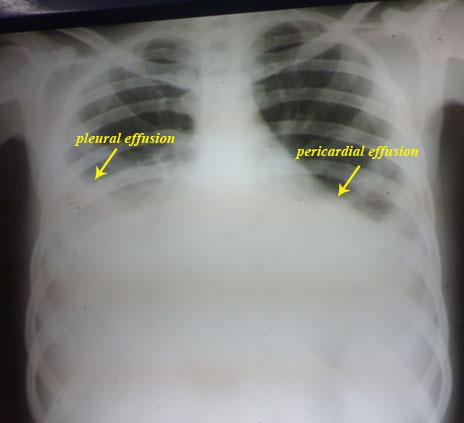

He sought medical advice that revealed bilateral pleural effusion,

then he was admitted in the chest department where both bilateral

pleural aspirates and biopsy studies revealed nothing "non-specific

pleurisy".

Now he presented feverish with facial flushing, oro-genital ulcers,

polyarthritis, lymphadenopathy, bilateral pleural and pericardial

effusion and ascites.